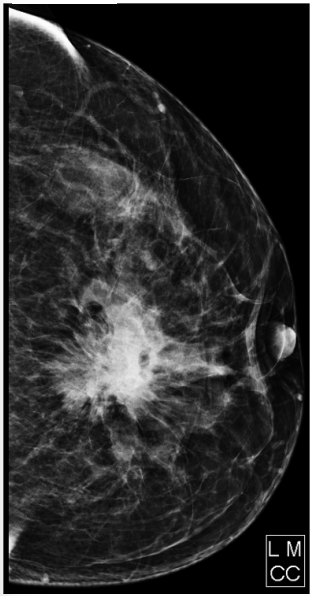

Paciente do sexo feminino, 65 anos de idade, comparece ao serviço para realização de mamografia, queixando-se de massa palpável

em mama esquerda e retração de papila. Com relação ao exame abaixo e ao sistema de classificação BI-RADS, assinale a alternativa

CORRETA.

Figura 3 – Mamografia.

Fonte: CPCON.

Figura 3 – Mamografia.

Fonte: CPCON.